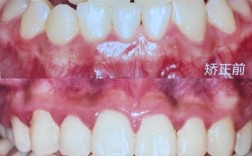

要确保对比图片的可比性,拍摄时的标准化操作至关重要,首先是时间节点,通常包括矫正前(T0期)、矫正中(每3-6个月动态记录,T1-Tn期)、矫正结束时(Tm期)及矫正后随访(矫正后1年、3年,Tm+1、Tm+3期),每个时间点的拍摄条件需保持一致,其次是拍摄角度,需涵盖正面、侧面(45°侧、90°侧)、上颌牙列像、下颌牙列像及咬合像,其中正面像需自然放松微笑,侧面像需保持耳屏鼻尖上唇三点一线,确保面部轮廓对称性,设备方面,建议使用专业口腔内窥镜相机,固定焦距、光圈及色温,避免手机拍摄因光线、距离变化导致的色差或变形,口内拍摄时,需使用牵拉器暴露牙齿,去除唾液和血液干扰,必要时使用咬合纸标记咬合接触点,以便对比矫正前后咬合关系的改善。

不同类型的错颌畸形,其矫正前后的对比重点各有差异,以下通过表格列举常见案例及观察要点:

| 错颌类型 | 矫正前表现 | 矫正后变化 | 对比图片关键观察点 |

|---|---|---|---|

| 牙列拥挤 | 上颌前牙“重叠排列”,牙冠宽度大于可用间隙,刷牙不易清洁,可能存在龋齿风险。 | 牙齿排列整齐,间隙均匀,弧度自然,口腔卫生维护难度降低。 | 牙列对称性、牙冠间“黑三角”消失、牙龈乳头形态恢复、邻接点紧密程度。 |

| 龅牙(深覆盖) | 上前牙明显前突,自然状态下上下唇不能闭合,微笑时牙龈暴露过多,侧面观“凸面型”。 | 上前牙内收,上下唇闭合自然,微笑时牙龈暴露减少,侧面轮廓线从“凸”变“直”或“微凹”。 | 上唇突度变化(E线:上唇与鼻尖关系)、颏部形态改善、鼻唇角增大、微笑曲线对称性。 |

| 地包天(反颌) | 下前牙咬在上前牙唇侧,下巴前伸,面下1/3变长,可能影响咀嚼功能及发音。 | 上下前牙恢复正常覆颌覆盖关系,下巴回缩,面下1/3比例协调,咀嚼效率提升。 | 咬合关系(上前牙舌面与下前牙唇面接触)、侧面下颌角形态、颏部突度变化、中线对齐情况。 |

| 开颌 | 上下前牙及前磨牙区无咬合接触,后牙咬合,可能导致咀嚼无力、发音不清、面部增长。 | 前牙区建立正常咬合,后牙区咬合稳定,面部垂直高度协调,发音清晰度改善。 | 前牙咬合接触点、后牙咬合面积、面部中下1/3比例、舌体位置是否正常。 |